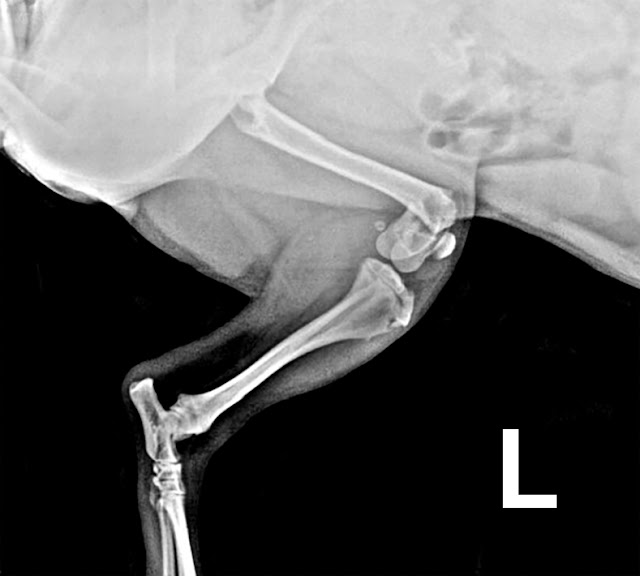

Fractura de húmero

Nuestro paciente es un perro recogido, un podenco de 12 kg,

con una cojera de no apoyo de su extremidad anterior izquierda. Comenzamos el

estudio radiográfico y se obtienen las siguientes imágenes:

Se trata de una fractura de húmero conminuta, supracondilar,

casi intercondilar y que me hizo dudar un poco al principio, con la primera

radiografía, donde no tenía claro si era también intercondilar y se hicieron

varias radiografías más hasta que logré la imagen que estaba buscando, y pude

comprender mejor la fractura.